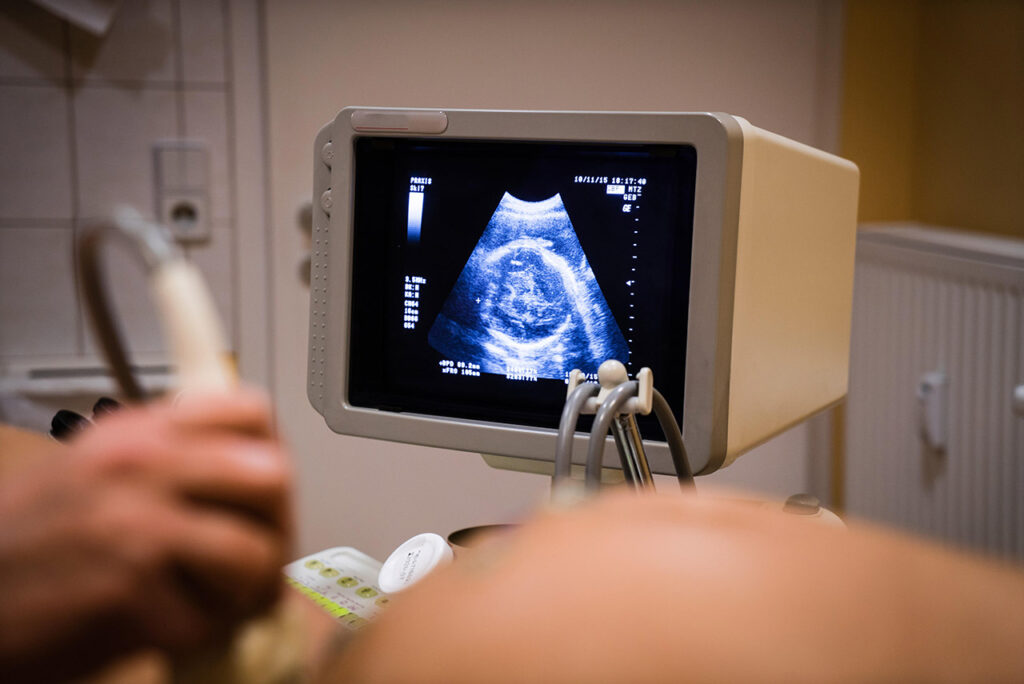

Паразитический близнец

Это редкая аномалия (один случай на миллион), когда один из близнецов перестает развиваться и остается прикрепленным к телу другого близнеца. В результате ребенок может родиться с дополнительными конечностями или органами. Такой ребенок сталкивается с высоким риском осложнений, нуждается в медицинской помощи и удалении лишних тканей. Эту аномалию обычно выявляют на УЗИ.